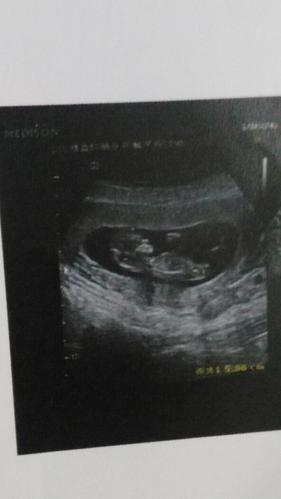

宝妈们谁照了11周的彩超发个图看看呗

- 怀孕11周男孩b超图